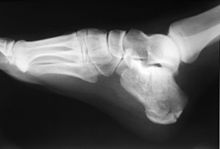

Calcaneus fracture X-ray

Normally the tibia sits vertically above the calcaneus (pes rectus). If the calcaneal axis between these two bones is turned medially the foot is in an everted position (pes valgus), and if it is turned laterally the foot is in an inverted position (pes varus).[4]